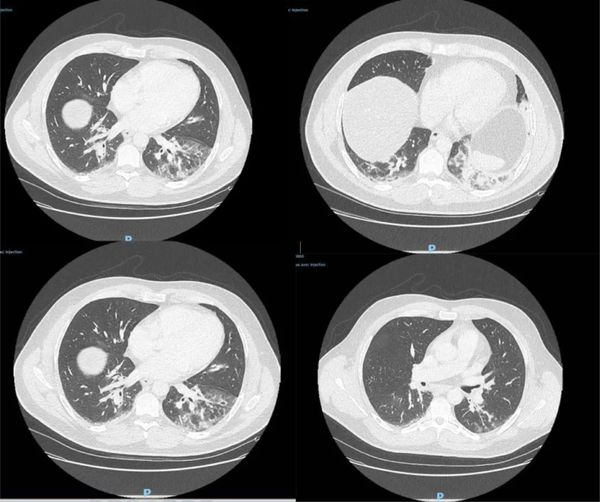

研究人员此番发现,一名42岁男子的样本新冠病毒检测呈阳性。该男子出生在阿尔及利亚,已长居法国多年,职业为鱼贩,最近一次旅行是在2019年8月前往阿尔及利亚。他于去年12月27日到急诊室就医,CT检查显示双侧肺下叶呈现磨玻璃影,并伴有咯血、咳嗽、头痛及发热症状,且当时症状已持续4天。病患当天被收入重症监护室并进行抗生素治疗,后因病情好转于12月29日解除重症监护。

△图为病患CT检测影像